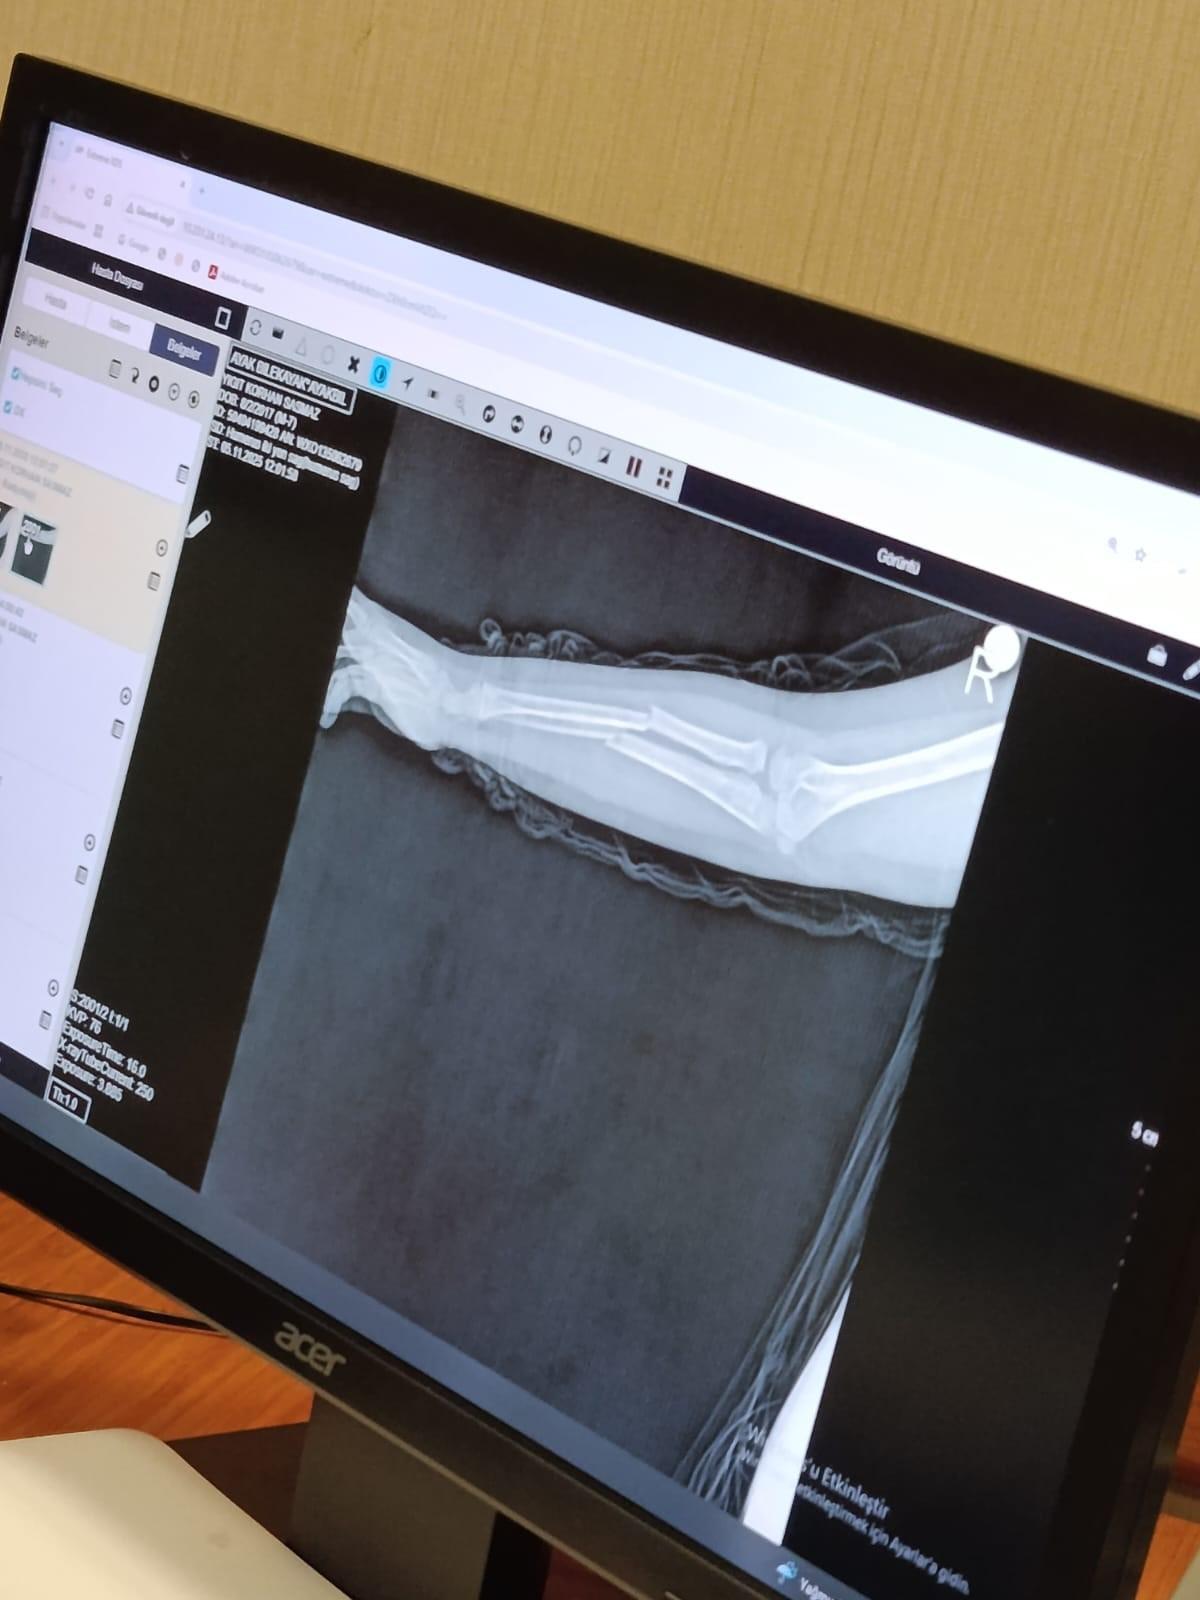

Olay, geçtiğimiz ay Büyükçekmece Tepecik'te bulunan bir ilkokulda meydana geldi. İddiaya göre 8 yaşındaki Y.K.Ş. okulda bir süredir kendisini rahatsız eden 9 yaşındaki çocuk tarafından darp edilerek kolu ikiye katlandı. Y.K.Ş.'nin 2'ye katlanan kolu 2 ayrı yerinden kırıldı. Öğretmenler Y.K.Ş.'nin ailesini arayarak, 'oğlunuz arkadaşıyla kavga etti duvara çarptı' denildi. Oğlunu okuldan alıp hastaneye götüren anne Songül Gökdemir, oğlunun kolunun 2 ayrı yerinden kırıldığını öğrenip ameliyata alınacağını duyduğunda büyük şok yaşadı. Konuyla ilgili anne Gökdemir savcılığa giderek şikayetçi oldu. Savcılıktan ise 'söz konusu Suça Sürüklenen Çocuğun yaşının 12'den küçük olduğu gerekçesi ile kovuşturmaya yer yoktur' kararı çıktı. Anne Gökdemir karara itiraz ederken mağdur Y.K.Ş. ise haftalardır okula gidemiyor. Eğitimi aksayan çocuğun 2 hafta sonra ise platinlerinin çıkarılması için yeniden ameliyata gireceği öğrenildi.

Yaşanan olayı anlatan Songül Gökdemir, " Arkadaşlarından darbe aldığını biliyordum. Ayrıca Eylül ayından bu yana bir arkadaşının onun kolunu kırmaya çalıştığını söyledi. Ben de 'arkadaşını öğretmene söyle' dedim. Bundan kaçıyordu. O gün de rehber öğretmenine bu arkadaşını şikayet ettiler. Ben işe gittim 1 saat sonra öğretmeni aradı. Oğlunuz arkadaşıyla birbirini itekledi kolunu duvara çarptı gelir misiniz ?' dedi. Kendi imkanımla hastaneye götürdüm. Okula gittiğimde de oğlum derste oturuyordu. Öğretmen ders işliyordu ambulans çağırılmamış. Hastanede kolunda 2 tane kırık olduğunu acilen de ameliyata girmesi gerektiğini öğrendim. 3 gün sonra ameliyata alındı. Kolundaki platinlerden dolayı her gün pansumanı var. 2 hafta sonra tekrar ameliyatı var" dedi.